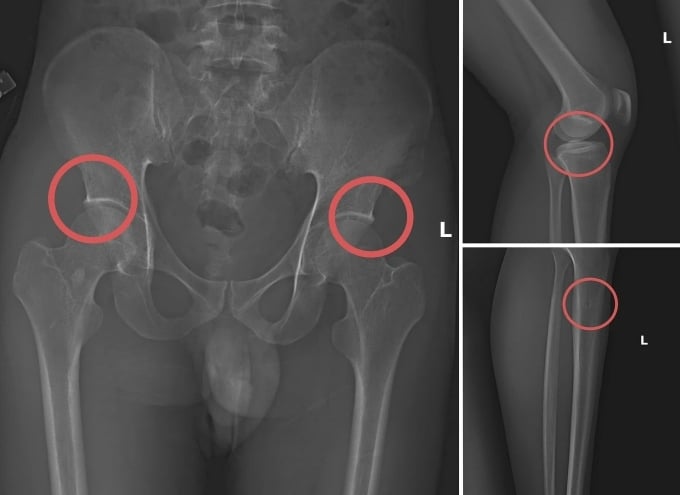

Trước đó, vụ án được cơ quan điều tra phát hiện sau khi tiến hành thu thập tài liệu liên quan. Tạ Minh Châu (30 tuổi, cựu cán bộ Trung tâm Y tế huyện Cẩm Khê – Phú Thọ) được xác định là chủ mưu, kẻ cầm đầu. Châu lợi dụng kinh nghiệm lâu năm trong ngành y, am hiểu cấu tạo xương và cơ chế chi trả bảo hiểm đối với thương tích gãy xương nên đã dựng lên một quy trình trục lợi bảo hiểm bài bản.

Đường dây này được tổ chức từ việc vận động người dân mua bảo hiểm, gây thương tích nhân tạo, cho đến hợp thức hồ sơ bệnh án để chiếm đoạt tiền. Khi thương tích đã được tạo ra, Châu cùng đồng phạm dựng hiện trường giả, từ điện giật đến trượt chân ngã suối, nhằm hợp pháp hóa hồ sơ yêu cầu chi trả.

Với thủ đoạn tinh vi này, nhóm đối tượng đã chiếm đoạt hơn 6 tỷ đồng từ nhiều công ty bảo hiểm nhân thọ. Hành vi này không chỉ vi phạm pháp luật mà còn đặt nạn nhân vào tình trạng nguy hiểm, có thể ảnh hưởng lâu dài đến sức khỏe, khả năng vận động và chất lượng sống.